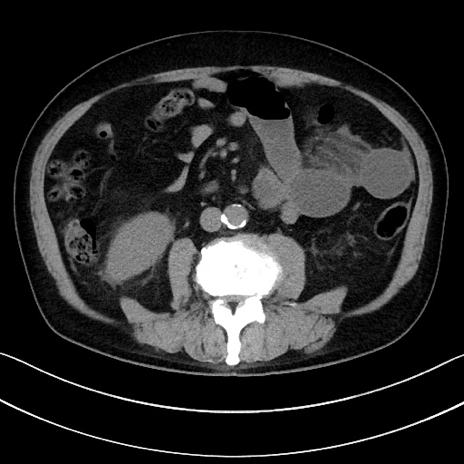

症例15(横断像)

【症例】70歳代男性

【主訴】腹痛

【現病歴】今朝から腹痛あり。全体的に痛い。特に左上の方。排ガスが今日はない。冷や汗が出る。

【既往歴】直腸癌術後

【身体所見】左側腹部〜上腹部に圧痛あり。腹膜刺激症状明らかなではない。軽度反跳痛。左下腹部に術後瘢痕あり。

【データ】WBC 7700、CRP 0.02